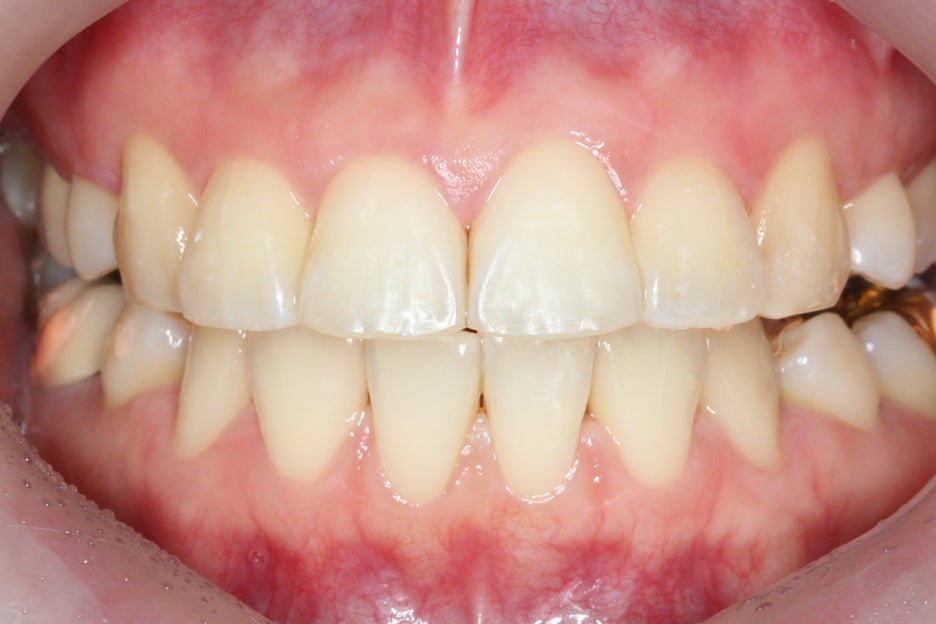

상하악을 개방하였을 때

보이는 아랫니의 배열도

앞쪽의 치열이 유난히

삐뚤거리는 상황인데요,

overbite 사진을 참고해보면

#11, #21 치아의 뻐드러짐과

돌출로 인해 전치부 교합이

잘 맞지 않는 모습을 확인할 수 있습니다.

아랫니의 돌출감도 상악에 비해

비교적 덜한 편이지만

치아 교정을 통해 개선할

여지가 있는 모습이네요.